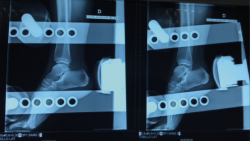

Figura 3. Radiografía en varo forzado. Tienen valor diagnóstico si son positivas. El varo forzado es positivo si existe un varo > 15° o una diferencia de > 10° respecto al tobillo contralateral.

- Varo forzado: positiva si existe un varo > 15° o una diferencia de > 10° respecto al tobillo contralateral (Figura 3).

- Cajón anterior: positiva si existe una traslación anterior > 1 cm o una diferencia > 3 mm respecto al tobillo contralateral (Figura 4).

Figura 4. Radiografía del cajón anterior. El cajón anterior es positivo si existe una traslación anterior > 1 cm o una diferencia > 3 mm respecto al tobillo contralateral.